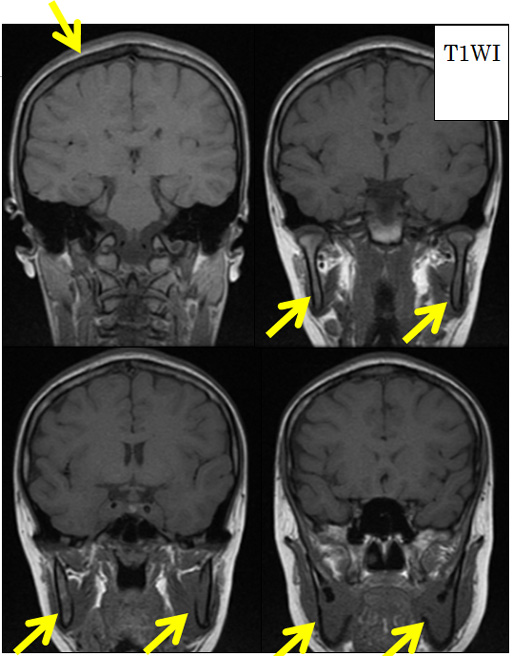

- 上顎骨、下顎骨、頭頂骨にT1WIで信号低下あり。